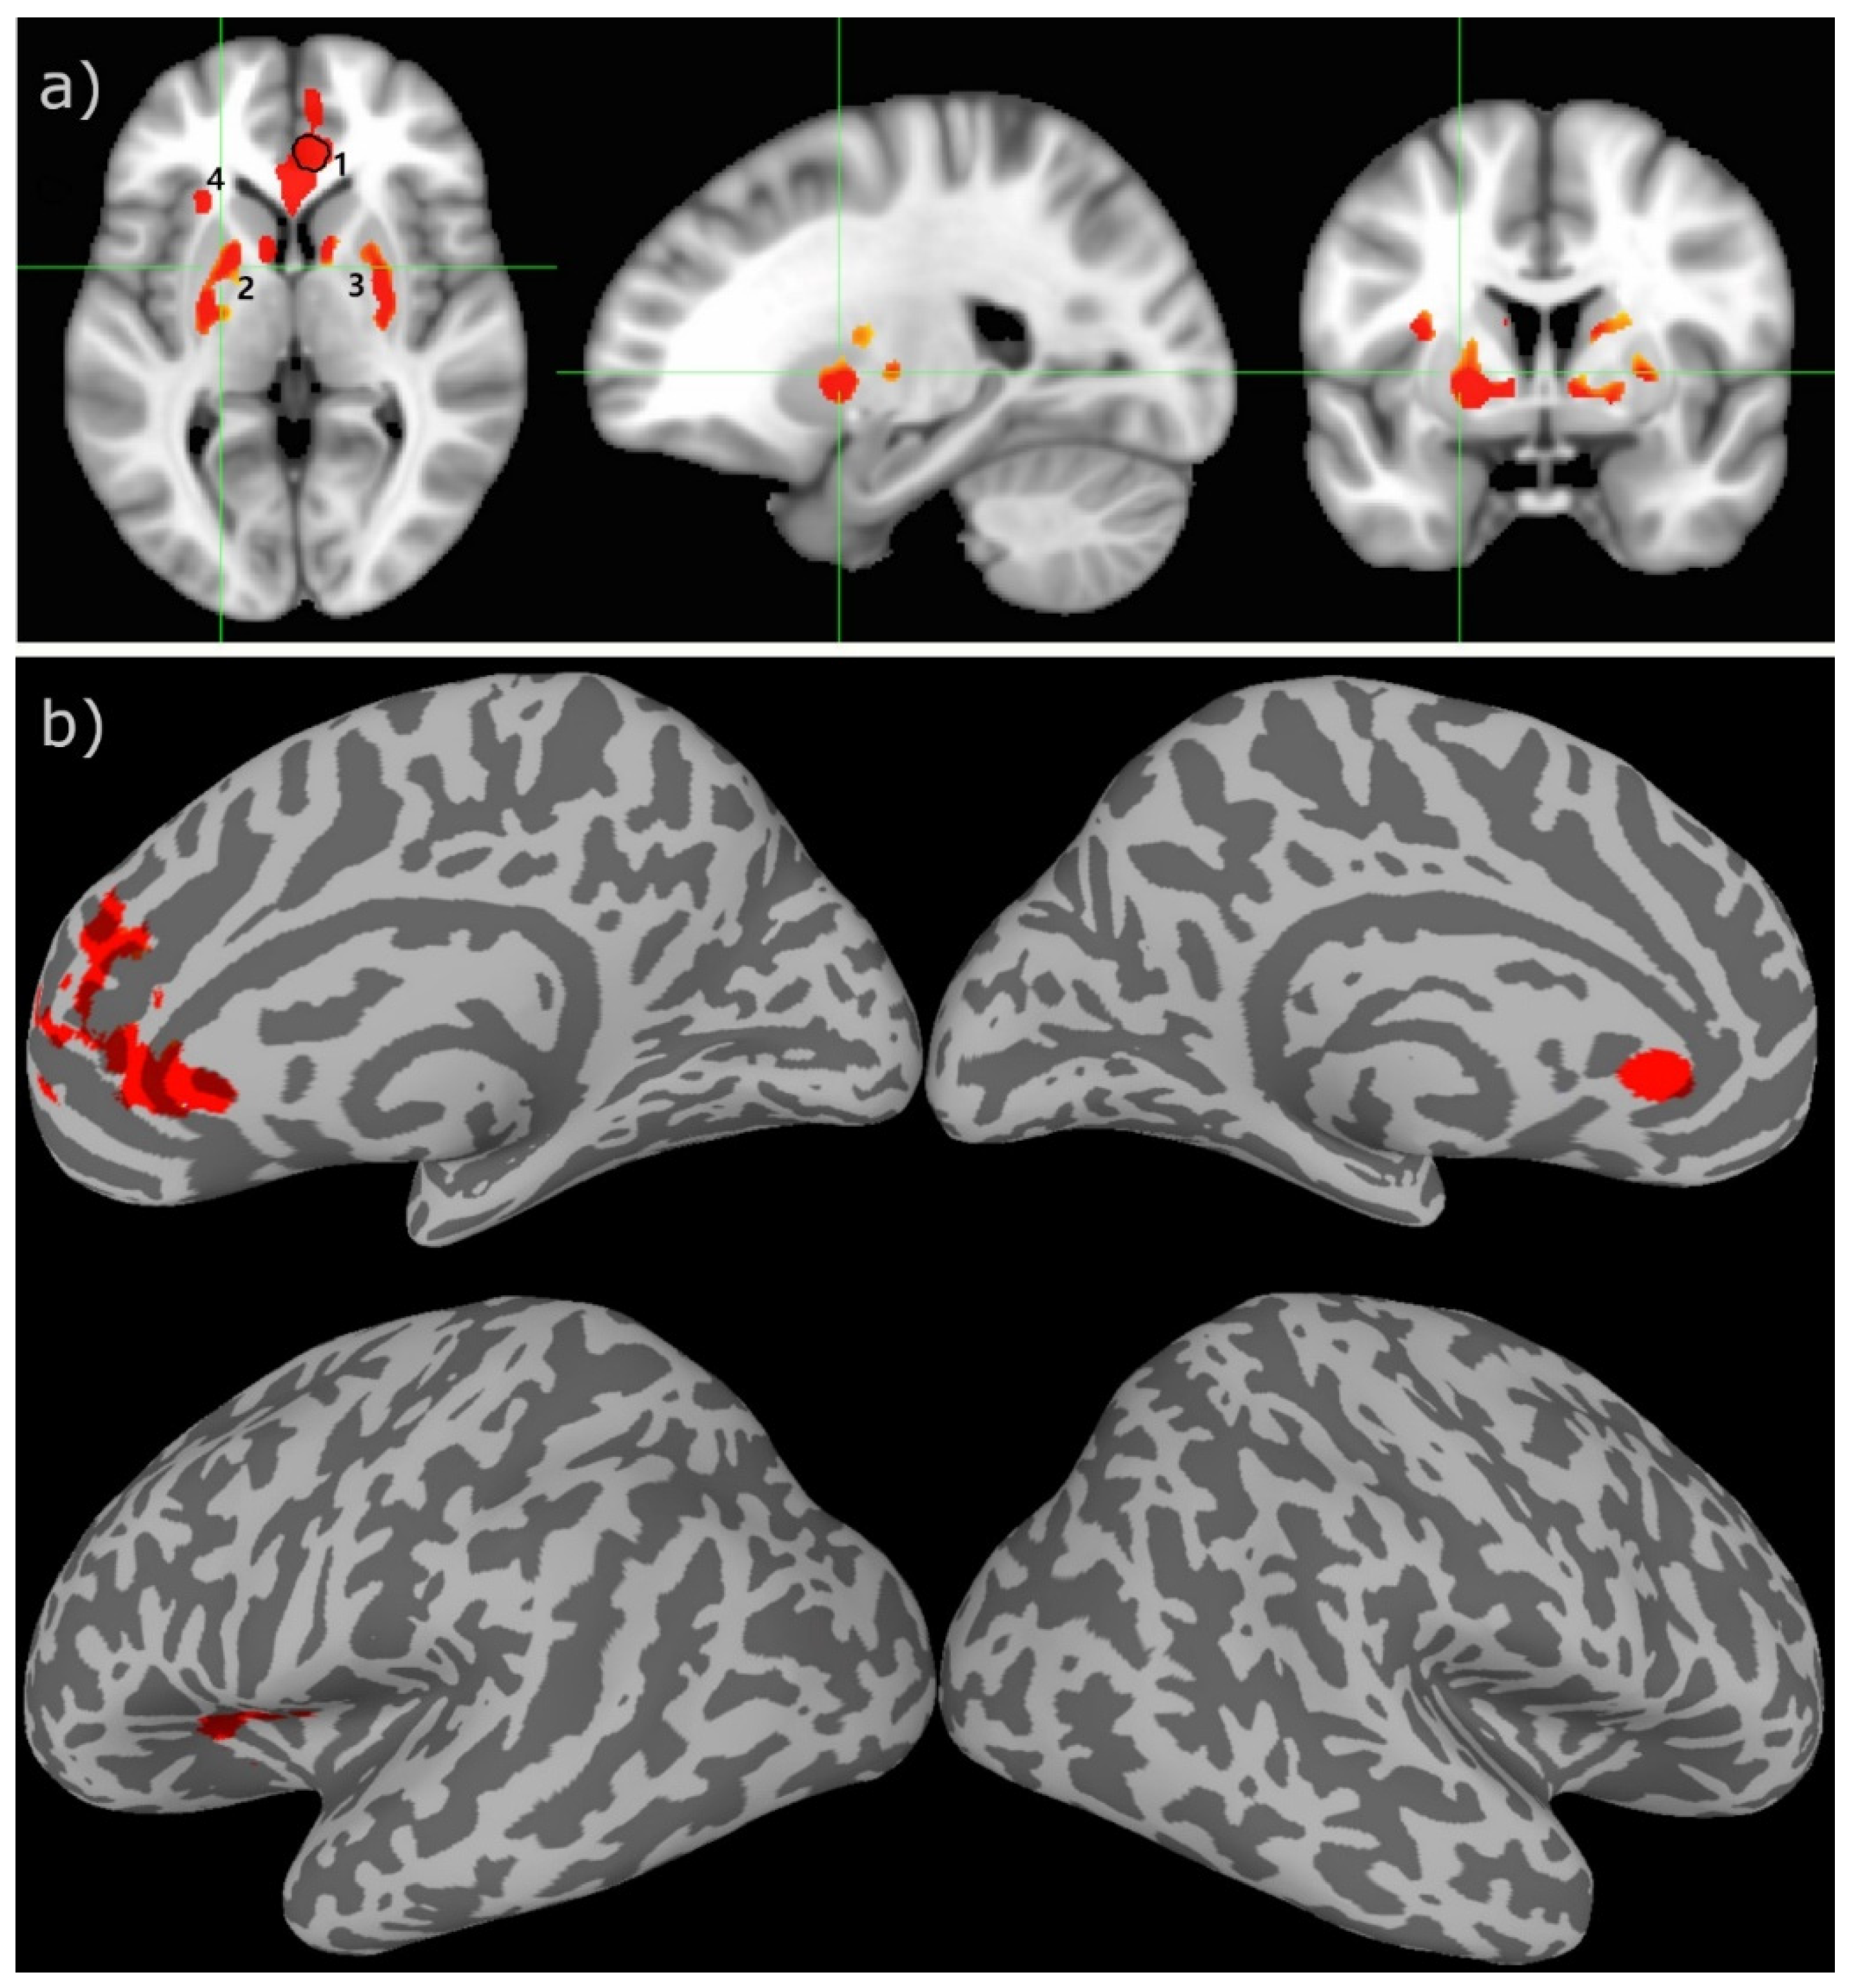

The two-sample t-test result of the rCBF measurements for the HC and ME/CFS subjects demonstrated that there is statistically significant hypoperfusion (FWER, p < 0.01) for the ME/CFS subjects in the limbic system. As shown in Figure 1 and Table 2, the main involved regions are in the limbic system, including the anterior cingulate cortex (ACC), left anterior ventral insular area, pallidum, and caudate nucleus. As depicted in the scattered boxplot (Figure 2), the ROI averaged rCBF for the HC and ME/CFS subjects in these detected regions was 57.9 ± 15.2 and 38.1 ± 8.4 mL/100 g/min, respectively. For the ME/CFS subjects, cerebral perfusion in these brain regions was reduced by about 34% in comparison with the HC group.

Figure 1.

The two-sample t-test results between the healthy controls versus the CFS patients overlaid on the MNI152 template in the cross-sectional displays (a) and inflated cortical surface (b). The green lines indicate the location of cross-sections. The numbers indicate the different ROIs ranked according to their sizes in descending order. The encircled area in ROI 1 indicates the brain region where the subjects’ rCBF values have a significant association with their VAS-f scores. The colored clusters indicate ROIs with t-scores ≥ 3.2 (uncorrected voxel wise p ≤ 0.001) and cluster size ≥ 200 voxels (survived FWE correction p ≤ 0.01).

The most important findings of this study are the following: (1) There are statistically significant differences in the cerebral rCBF between the ME/CFS patients and adult healthy controls. The involved brain regions are localized in the limbic system, including the ACC, prefrontal cortex, left anterior ventral insular area, pallidum, and caudate nucleus. (2) The ROI averaged rCBF in the ACC is significantly correlated with the ME/CFS patients’ EQ-VAS scores, as detected by voxel-wise linear regression analysis.

As shown in Table 2 and Figure 1 and Figure 3, the brain regions with hypoperfusion are localized in the limbic system, and there is a tendency that the further reduced rCBF is associated with more severe fatigue symptoms, although this association is not significant. The small range of the FSS score might have limited its sensitivity to measure the level of fatigue. In contrast, the range for EQ-VAS is much larger, and it is more likely to provide a finer graded measure for fatigue severity. As discussed above, the EQ-VAS was significantly associated with rCBF for a cluster localized in the ACC (see Figure 1 and Figure 3). In a previous study of mTBI patients with chronic fatigue [18,19], it was also reported that there was a significant association between the self-rated fatigue of post-PVT performance and the rCBF reduction in the ACC. It is well known that the ACC plays an important role in performance monitoring and cognitive control [49]. Hypoperfusion in the ACC can, therefore, lead to impaired monitoring function and cognitive control of the brain. It has been hypothesized that an inability to predict the amount of energy demands for the required performance may underly mental fatigue [43,50]. This implies that the ME/CFS subjects may have an impaired ability to evaluate or adapt to the energy demands to sustain the performance of demanding tasks, which can easily lead to self-rated fatigue.